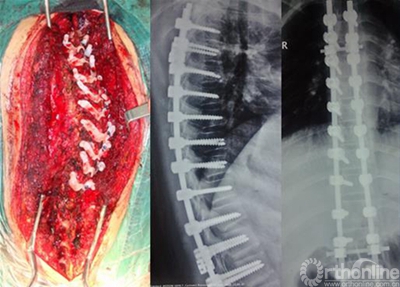

脊柱侧弯(术后)(非医学专业勿点)#medicalt 来自医学生Medic - 微博

脊柱外科的医生正在对脊柱侧弯患者实施手术